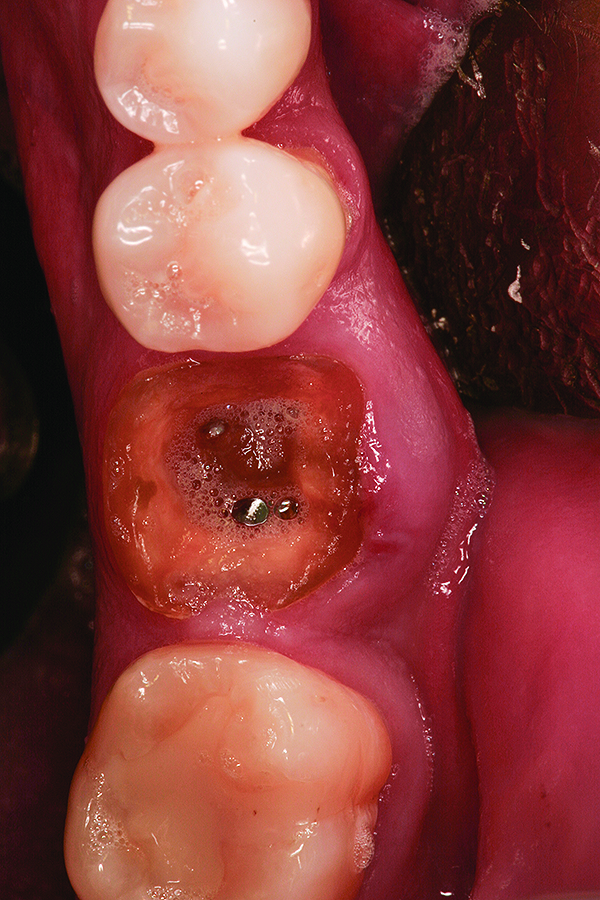

Fig 10. Placement of bone allograft into extraction site with collagen membrane on buccal aspect for graft containment.

Figure 10

Fig 12. Note the significant formation of bone and repair of the buccal osseous defect at 3 months healing.

Figure 12